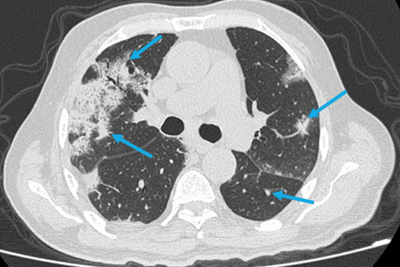

入院第2天,患者报告呼吸系统症状恶化,胸部听诊出现吸气性爆裂音。胸部X线检查显示片状间质浸润;胸部CT检查

显示双肺弥漫性浸润和实变(图2)。

(图2 胸部CT检查)